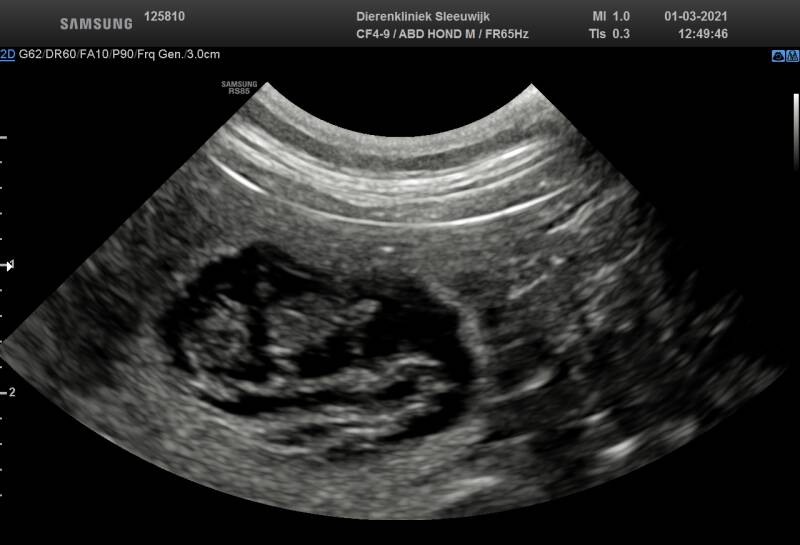

De echo's van 01/03/2021.

Deze echo's zijn gemaakt op 1 maart 2021.

Het moment dat we er achter kwamen dat Noesja 4 weken drachtig is.

Op deze echo foto's waren de puppy's 1,5 cm.